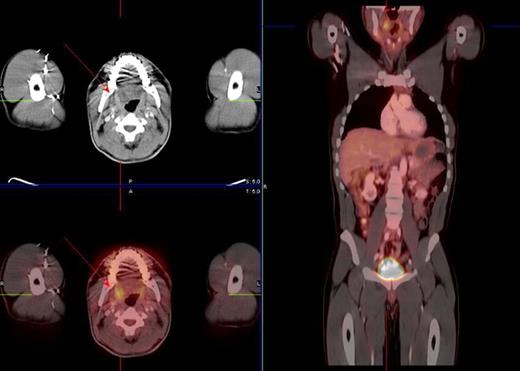

Restaging PET scan showing increased FDG tonsil uptake (red arrows) in a 38-year-old male patient with Hodgkin's disease stage II status post ABVD chemotherapy. Tonsillectomy was negative for malignancy.

All 8 tonsillectomies and FNA biopsies performed after a restaging PET that showed increased tonsil uptake were negative for malignancy (Figure 2). All of these 8 patients had an initial previous PET that did not show increased tonsil uptake and also these 8 patients remained in remission from their lymphoma after the procedure was performed. In contrast, 6 out of 7 patients that underwent tonsillectomy or FNA at diagnosis were positive for malignancy (Table 3). Differences among tonsil FDG uptake has been thought to reflect differences in activity of “physiological” inflammation of the palatine tonsils. Increased glucose metabolism during active inflammation in the case of chronic tonsillitis or lymphocyte proliferation in the case of a patient that has received prior chemotherapy (likely experiencing compensatory extra medullar lymphoid hyperplasia) were thought to be causes of high FDG uptake in the tonsils. The significance of such increased tonsil FDG uptake is currently unknown however previous studies suggest that normal pharyngeal palatine tonsil uptake was generally symmetrical and that the difference in maximal standardized uptake value (SUVmax) between right and left tonsils (right-to-left ratio or a surrogate of symmetry) in the same patient might be helpful in detecting malignant tissue. The mean right-to-left ratio of tonsillar SUV was 4.55 in patients with confirmed malignant pathology and 1.53 in patients with documented benign tonsillar tissue (Table 4). The mean tonsillar SUVmax was 15.35 in patients with confirmed malignant pathology and 7.05 in patients with documented benign tonsillar tissue hence SUVmax seems to be useful in differentiating tumor from physiological accumulation. Younger patients with low SUV max symmetric tonsillar uptake and no other abnormal FDG areas seen during restaging PET could probably be watched non-invasively.